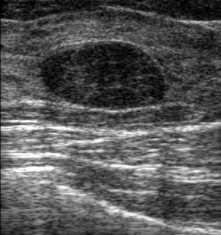

Gambar Ultrasonografi Payudara menunjukkan antara massa kistik (berisi cairan) dan padat

Kista Payudara - lebih banyak penampilan "hitam" untuk mengisyaratkan bahwa cairan itu berisi cairan